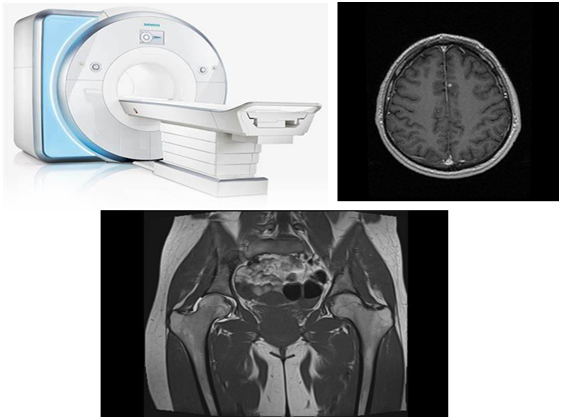

Магнитно-резонансная томография

Магнитно-резонансная томография чаще всего применяется для обнаружения каких-либо изменений при исследовании головного мозга и малого таза. Кроме того, врачи оценивают не только сам онкологический процесс, но и все возможные сопутствующие патологии, если они визуализируются.